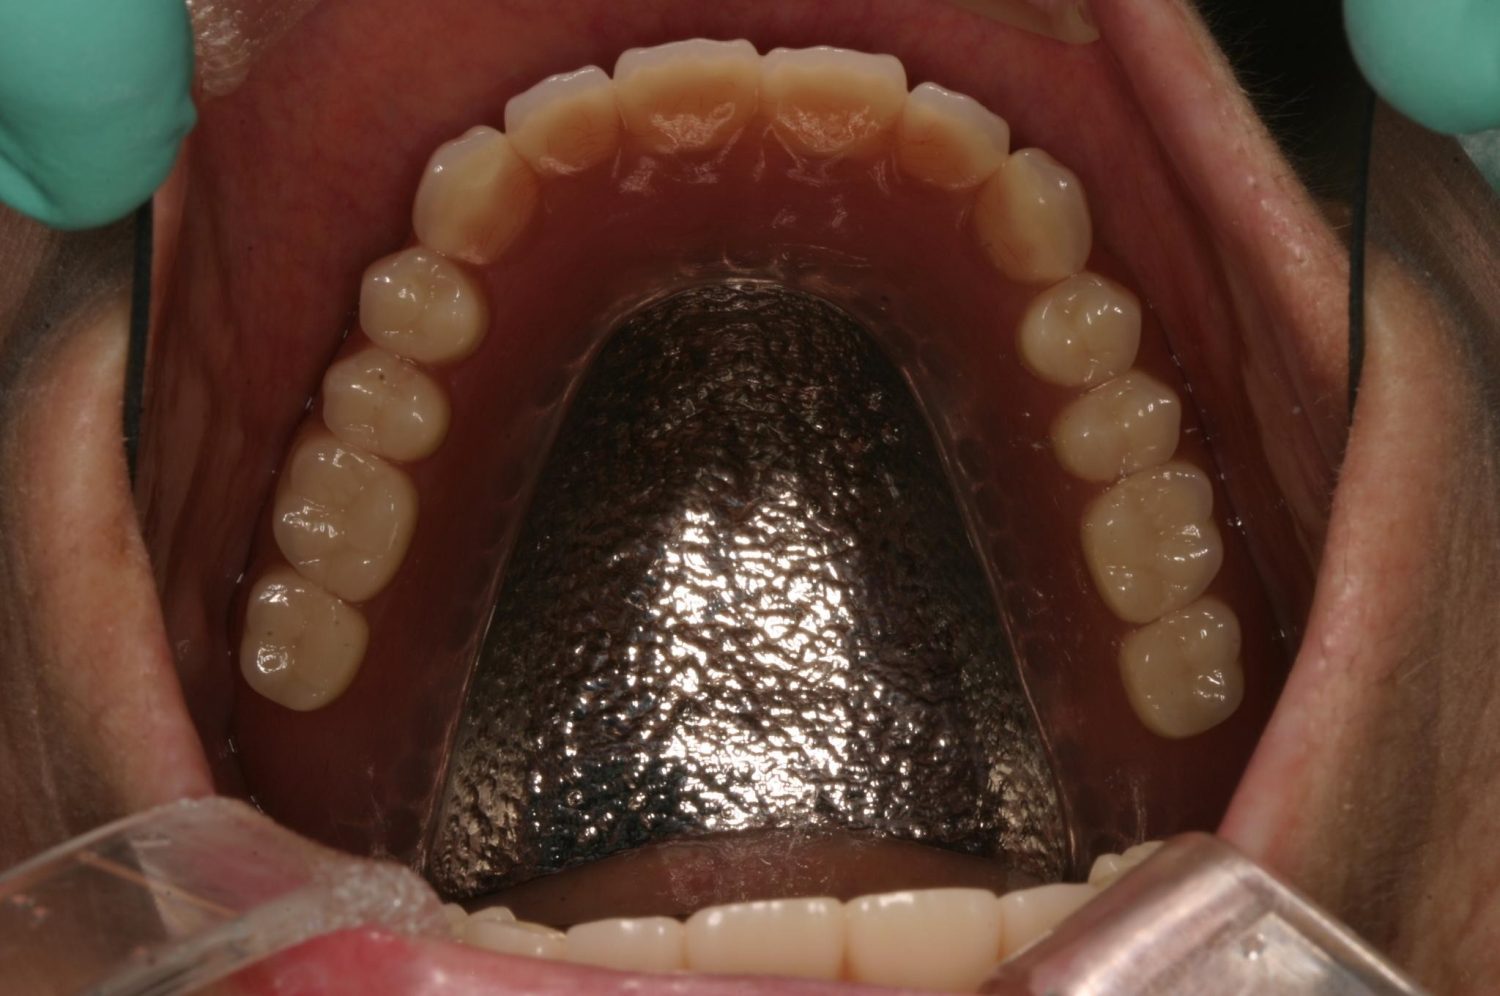

インプラント治療の症例紹介④

Before

After

主訴

義歯による疼痛

治療内容

下顎舌側に骨隆起があり義歯困難な状態。保存不可能な歯の抜歯を行い、インプラントを埋入し咬合再構成を行った。

治療費

2,851,200円(税込)

治療期間

29ヶ月

通院回数

26回

想定されたリスク

※咬合力の強い方なので、予防的にマウスピースの装着が必要。インプラント周囲炎の恐れがありました。

歯の欠損の対合歯の挺出等を修正し咬合平面を揃え咬合再構成を行った症例。